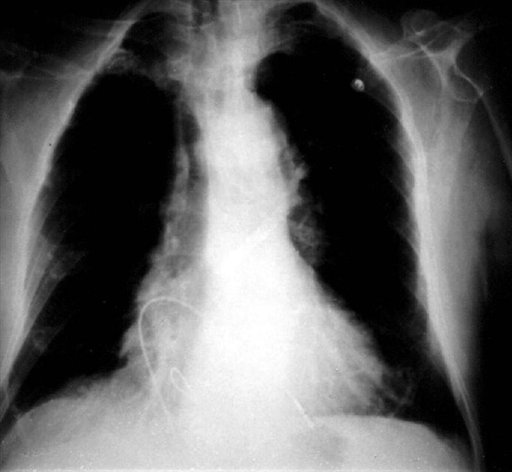

Ingeniero colombiano crea un marcapasos del tamaño de un tercio de un grano de arroz

Bogotá, 21 ago (EFE).- El ingeniero electrónico colombiano Jorge Reynolds, creador del primer marcapasos hace 53 años, anunció este fin de semana el lanzamiento de un dispositivo tan grande como un tercio de un...